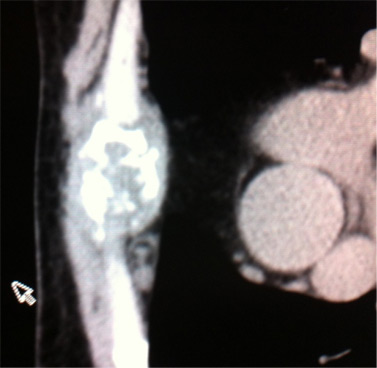

A 44 year old non-diabetic male presented with pain in upper central chest (manubrial area) for 9 months. along with tenderness over costochondral junctions on both sides of manubrium. The pain was not associated with swelling or any inflammation. There was no history of chest infection, fever or any other constitutional symptoms. General physical examination did not reveal any significant lymphadenopathy. His systemic examination was unremarkable. Accordingly, he was treated for costochondritis with NSAIDS without any improvement.  Subsequently, he was investigated for heart disease and his chest X-ray, electrocardiogram, echocardiography and treadmill test were negative. Non response to pain killers prompted a search for underlying disorder. Laboratory results showed TLC 9000 with differential of P61 L36 ESR 28mm. HIV and C-reactive protein were negative. Mantoux was reported to be 20 mm. Later, his chest pain progressed to involve right side over the lower ribs along with fever. Sputum examination was negative for acid fast bacilli. CECT chest suggested a diagnosis of sternal tuberculosis   revealing destructive lesion of manubrium with some enlarged mediastinal lymph nodes [Fig.1]. Repeat X-ray of the chest showed right sided pleural effusion [Fig.2]. Aspirate from effusion was negative for acid fast bacilli but PCR was positive for tuberculosis. CT guided needle biopsy from sternum yielded haemorrhagic fluid which was negative for AFB. Open curettage biopsy of the manubrium was done. Histopathology examination revealed classical picture of tuberculosis with caseous necrosis and epitheloid giant cells.  He was put on directly observed treatment, short course anti-tuberculous therapy and his chest pain gradually subsided.

Fig.1 : CT scan of sternum showing destructive lesion